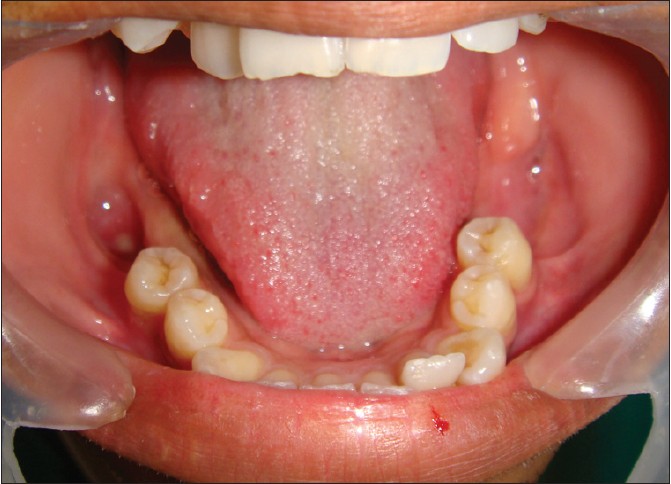

| Figure 12: Intraoral clinical view after 6 months showing the healing of bony cavities

Click here to view |

| Figure 13: Postoperative panoramic view after 5 months of enucleation showing significant amount of bone formation